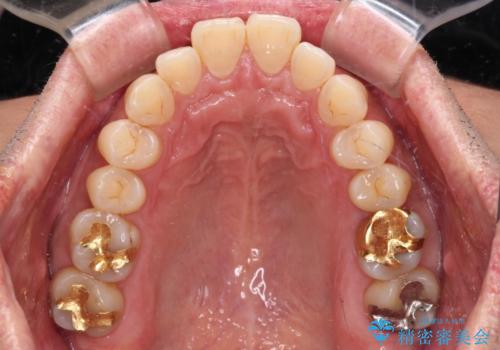

- 口元の突出感を気にして来院された患者様です。

強い咬合力と上顎前歯の傾斜により前歯が突出し、唇が閉じにくい状況であったため、上下左右の第一小臼歯4本を抜歯し、ワイヤー装置にて矯正治療を行うこととしました。

非常に咬合力が強いため、抜歯したスペースが閉じるのか不安でしたが、順調に歯が移動し、予定よりも早く治療を終えることができました。